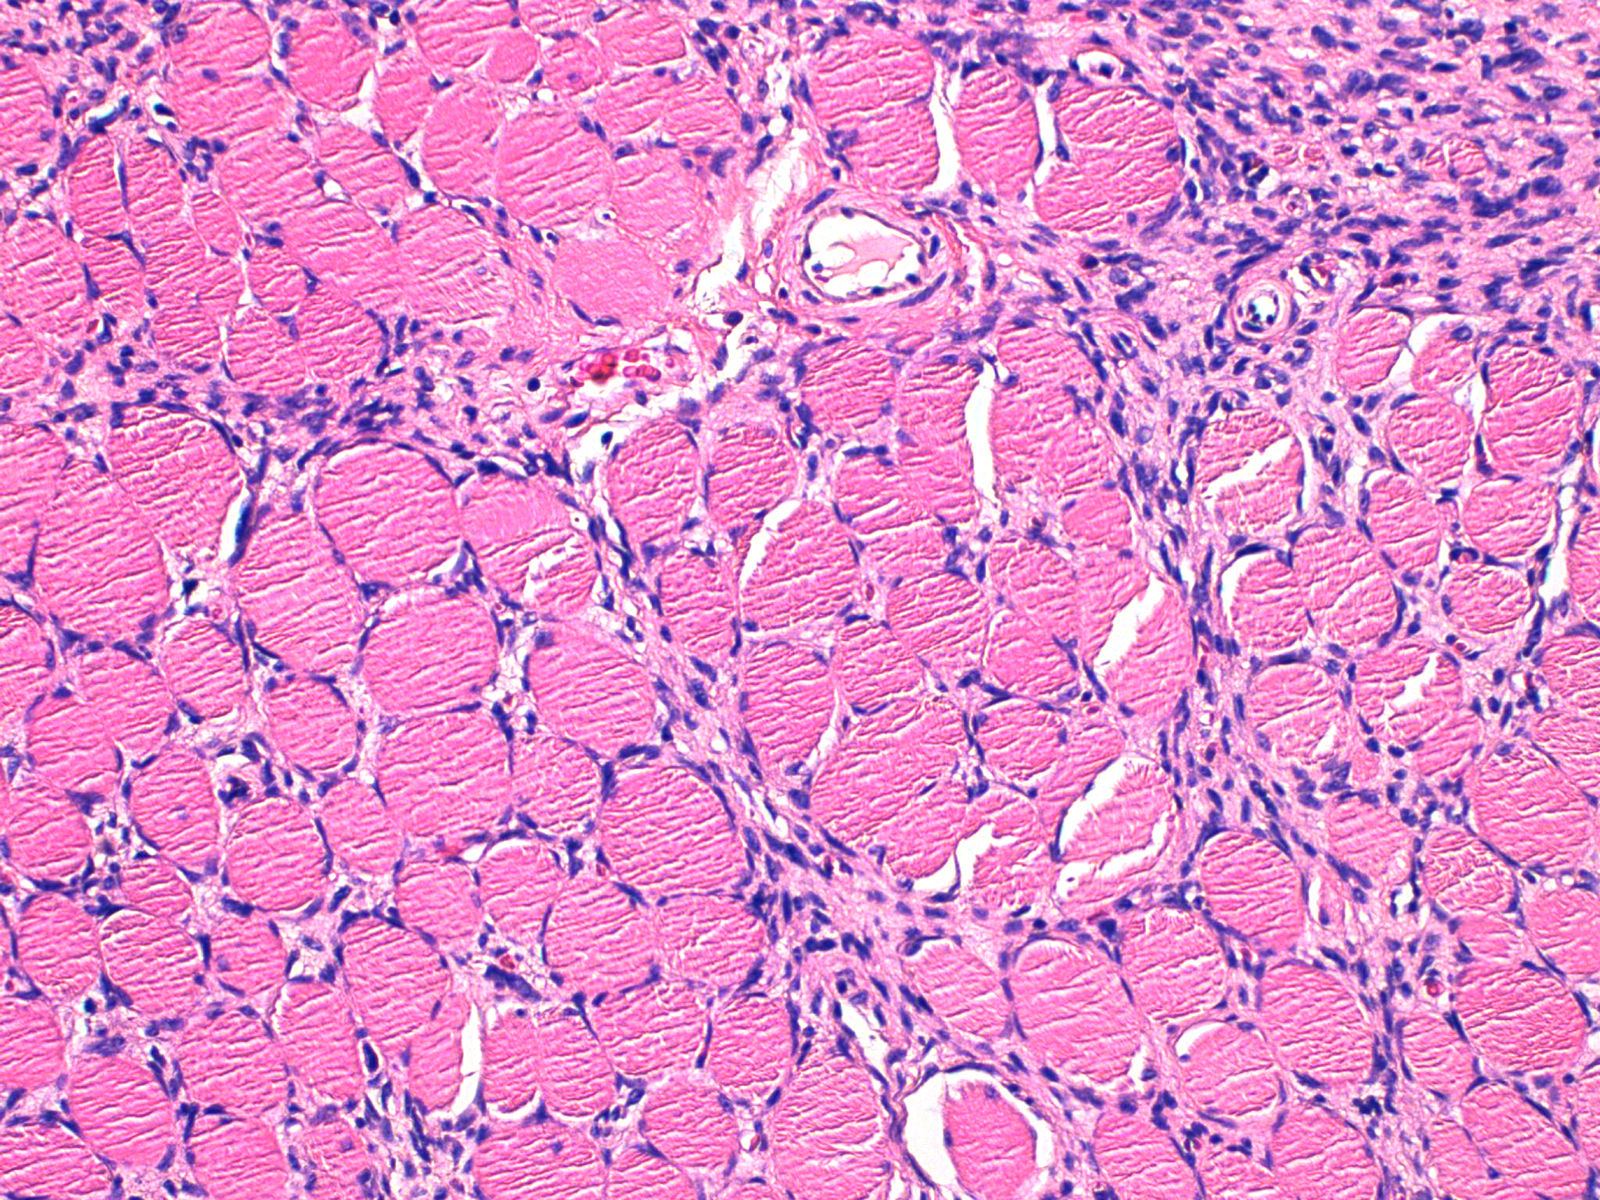

Histologically, all lesions showed a moderate proliferation of spindle cells with mild pleomorphism and CD34 positivity. No differences in CD34 staining pattern or intensity were observed according to tumor location. Most tumors showed storiform and cartwheel patterns (204/235, 86.8%). The compressive pattern of subcutaneous tissue infiltration was more common in head DFSP than in body DFSP (12/32, 37.5% vs 26/203, 12.8%; P=.005). No association was found between histologic subtypes previously described in the literature and tumor location. SC-DFSP was significantly more common on the head than elsewhere on the body (23/32, 71.9% vs 15/203, 7.4%; P<.001) (Figs. 2 and 3). Among head DFSP, time to diagnosis was shorter for SC-DFSP than for D-DFSP (68.3 vs 195.4 months; P=.005) (Table 2). Head DFSP also showed a greater tendency to invade deep structures, with focal infiltration of muscle or periosteum more frequently than body DFSP (26/32, 81.3% vs 38/203, 18.7%; P<.001) (Fig. 4).

Focal muscle infiltration, involving superficial muscle fibers immediately beneath the fascia, was observed in 9 of 10 facial DFSP (90.0%). However, none of the facial DFSP infiltrated the periosteum. In scalp DFSP, tumor extension reached the periosteum in 11 of 22 cases (50.0%; P=.009). No bone involvement was found in any of the 235 tumors. The fibrosarcomatous subtype was present in 38 of 235 tumors (16.2%), with no difference according to tumor location.